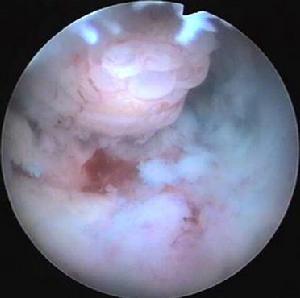

子宫内膜息肉子宫内膜息肉是由于宫内膜增生过盛构成,任何年龄均可发生,很常见的类型的局限性的内膜肿物,突出于子宫腔内、光滑、肉样硬度,蒂长短不一,长者可突出于宫颈口外,有的蒂较短。凡借细长的蒂附着于子宫腔内壁的肿块,临床上都可称为子宫息肉。因此,在宫腔内的息肉样肿块,可能是有蒂的粘膜下肌瘤、子宫内膜息肉、子宫腺肌瘤样息肉和恶性息肉(癌或肉瘤)。较小的息肉一般无临床症状。有的露出宫颈外的息肉在房事后流血就诊被发现。对蒂较长者可在宫腔镜直视下用激光手术切除,对同时发现的较小的息肉一并处理。子宫息肉是腔内镜下激光手术的最佳适应症。

子宫内膜息肉大体观察,最常见的类型是局限性的内膜肿物突出于子宫腔内,单个或多发,灰红色,有光泽,一般体积较小,平均直径在0.5~2cm之间。小的仅有1~2mm直径,大而多发者可充满宫腔。蒂粗细、长短不一,长者可突出于子宫颈口外。有的蒂较短,呈弥漫型生长。息肉表面常有出血坏死,亦可合并感染,如蒂扭转,则发生出血性梗死。

子宫内膜息肉主要症状为月经量增多或不规则子宫出血;宫颈口处看到或触及息肉,子宫体略增大;作宫腔镜检查或分段诊刮,将取出的组织或摘除的息肉送病理检查,可以明确诊断,并可与功能失调性子宫出血、粘膜下子宫肌瘤及子宫内膜癌等鉴别。 医学百科网 | YxBaike.Com

3、根据探知的宫颈深度,调整子宫镜限位器,将子宫镜插入宫颈管,过内口,循子宫壁一侧缓缓推入到宫腔内。开启冷光源,打开注水阀门,嘱助手通过加压器,向宫腔内注入膨腔液。压力维持在18~22kPa(130~160mmHg)之间。在膨宫良好的可视空间仔细寻找子宫息肉蒂部的准确位置。自宫镜活检孔道,通过橡胶帽插入Nd∶YAG光纤,直视下,光纤插入息肉根部,输出激光,根据息肉根部大小调整激光输出功率。直至息肉变成绛紫时,能从基蒂部切下者一并切除。对无蒂及较小息肉者,可直接插入凝固,发白停止。